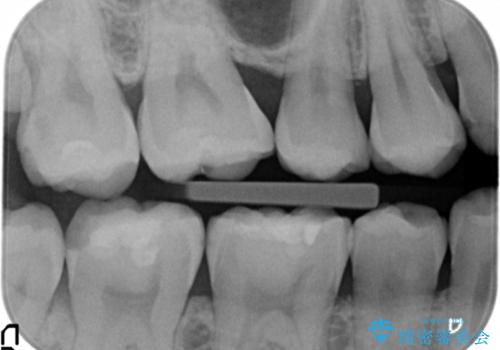

精査したところ、奥歯に充填された保険内のコンポジットレジンの適合が悪いことにより、汚れがたまりやすい状態でした。

不適合なレジンを除去し、セラミックインレーによる治療を行いました。(右上76左上67右下7の計5本)